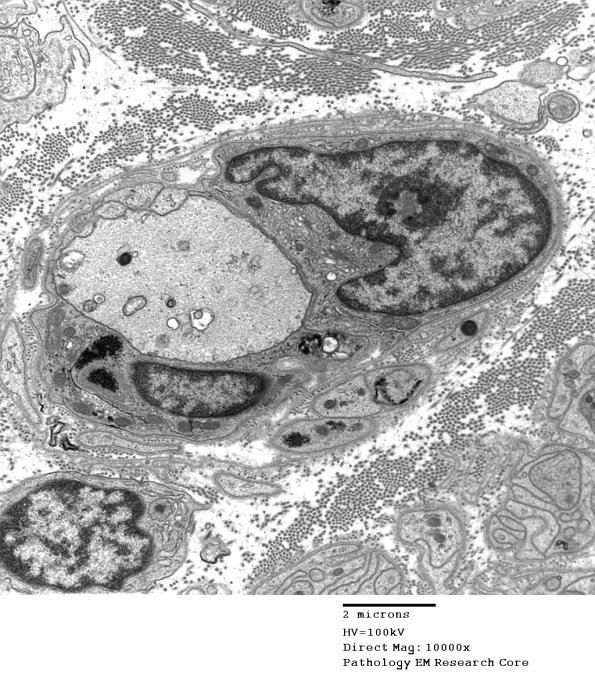

4B11,12 There is prominent reactive Schwann cell Golgi apparatus surrounding this demyelinated axon. (electron micrographs)